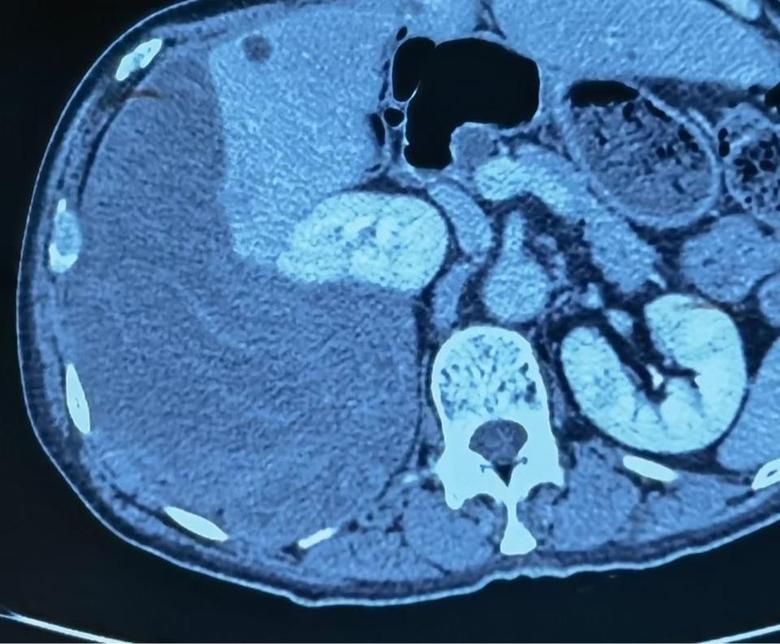

病例1

今日下午,2例巨大腹膜后肿瘤手术在我科顺利开展,腹膜后肿瘤发病率低,手术难度大,手术风险大,国内开展相关手术单位为数不多,我院腹膜后肿瘤手术量连续数年位居国内前列,在腹膜后肿瘤领域团队具有丰富经验,巨大腹膜后肿瘤手术开展,表明该类手术在我院已经成为常态。并且将继续保持国内在领先水平。